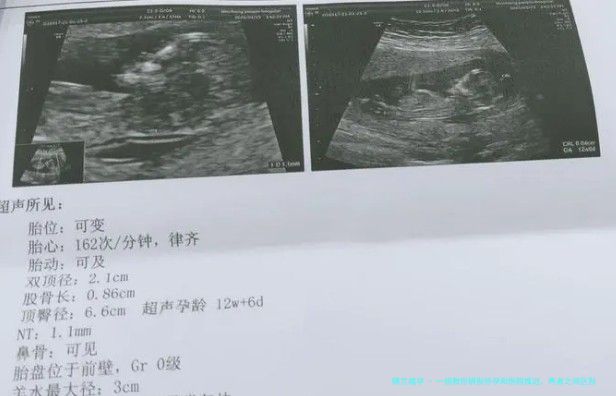

3.B超检查

例假延迟太长时间,除了怀孕的要素怀孕,还存留病症要素,因而这会儿可以到医院检查,并且也能够通过超声看到宫腔体内妊娠囊和卵黄囊,如此就可以通达是不是怀孕,如若未孕的话,通过B超亦可以认识内膜的厚薄程度,如若内膜稍薄的话,就会导致例假延迟。